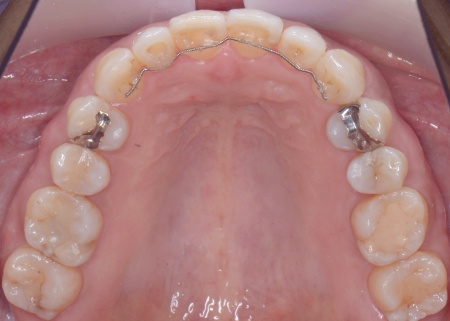

矯正方法としては、上下の歯全体の表面にブラケットと呼ばれるボタン状の装置を接着し、そこにワイヤーを通して歯を動かすマルチブラケット装置を採用しました。

とくに上の左右奥歯には、矯正用ミニインプラント(矯正治療専用の小さなネジ)を埋入し、奥歯を歯茎の方向に押し下げる「圧下」という治療を行っています。これにより開咬が解消され、前歯でしっかり噛めるようになりました。

マルチブラケット装置で矯正治療中です。